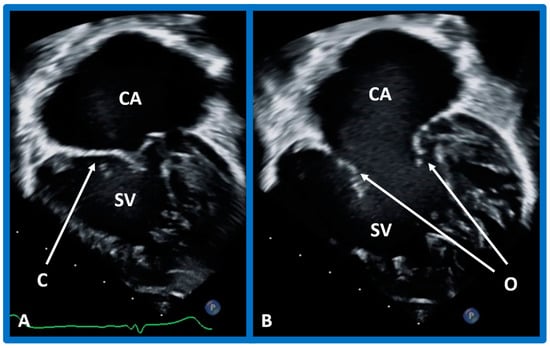

5.4. What Is the Status of Atrioventricular Connections?

After the visceroatrial situs and the ventricular locations are defined, the relationship between atria and ventricles should be assessed. These relationships are: concordant, with the RA emptying into the RV and the LA emptying into the LV (Figure 30A), and discordant, with the RA emptying into the morphologic LV and the LA emptying into the morphologic RV (Figure 39). Other AV connection abnormalities are: both the right and left atria emptying into a single ventricle (double-inlet left ventricle (Figure 30B)), both atria emptying into both ventricles via one common AV valve in the form of AV septal defect (Figure 42), a common atrium emptying into a single ventricle via a single AV valve (the so-called cor biloculare) (Figure 43), a common atrium emptying into inverted ventricles via a single AV valve (Figure 44) and atresia of either tricuspid or mitral valve (Figure 45). In addition, straddling or overriding of the AV valve over the ventricular septum may also occur. Such abnormalities may be defined by methodical echocardiographic imaging with the rare need for MRI, CT, and angiographic studies.

Figure 42. Echo images in apical four-chamber projections demonstrating the connection of a common atrioventricular valve with the right (RV) and left (LV) ventricles. In (A) (small arrows), the atrioventricular (AV) valve is open, whereas the AV valve is closed in (B,C) during varying phases of the cardiac cycle. Atrial septal defect of ostium primum (PASD) type of large size in (B), as well as a large ventricular septal defect (VSD) in (C), are illustrated. LA, left atrium; LV, left ventricle; RA, right atrium; RV, right ventricle. Replicated from reference [41].

Figure 43. Echo frames in apical four-chamber views demonstrating a connection of common atrium (CA) with single ventricle (SV) by a one (common) atrioventricular valve. In (A), the common atrioventricular valve is closed (C), whereas in (B), it is open (O). Heavy trabeculation is seen in the SV.